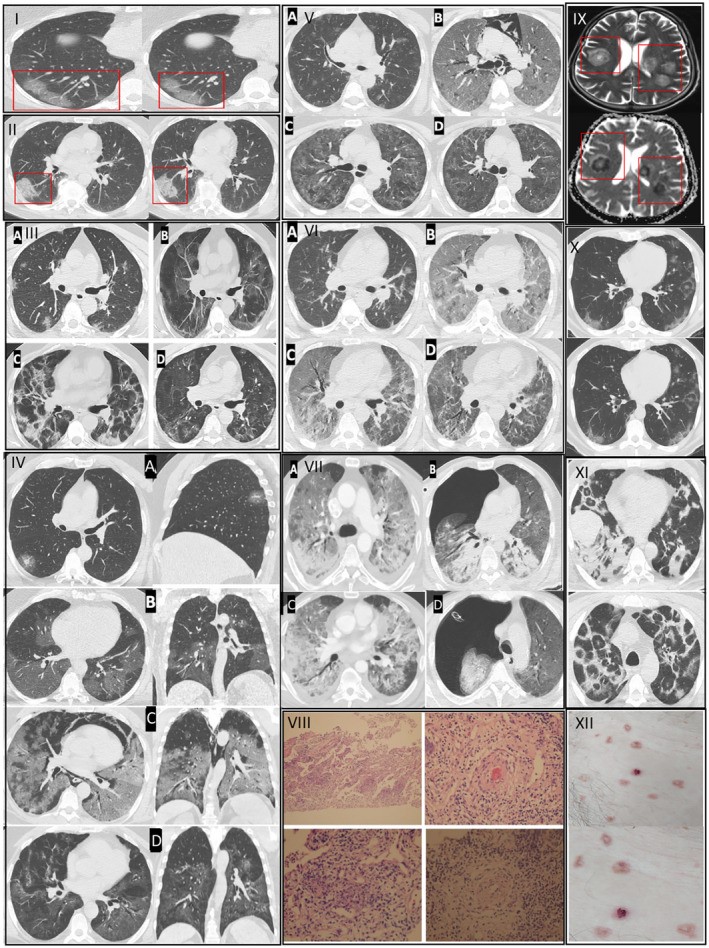

Prof. Dr. Özkaya, Kovid-19'un özellikle kılcal damar düzeyinde ciddi hasar bıraktığını belirterek, "Pandemi boyunca takip ettiğimiz binlerce hastada ‘endotelit’ dediğimiz damar iç yüzeyi hasarının ani ölümleri tetiklediğini saptadık ve uluslararası dergilerde yayınladık. Avrupa Kalp Dergisi’nin son verilerinde de bu durum ‘Kovid-19 sonrası damar yaşlanmasının hızlanması’ olarak tanımlanmıştır. Virüsü geçirenlerde damar yaşı, takvim yaşından daha yaşlı hale geliyor. Bu etki bazı kişilerde 5 yıllık yaşlanmaya eşdeğer" dedi.

Özkaya, Kovid-19 sonrasında yoğun egzersiz yapan gençlerde ani kalp krizlerinin görülebildiğini belirterek şunları söyledi: "Pandemi öncesi yaptığı ağır sporları aynı şekilde sürdüren bazı kişilerde ciddi kalp ve akciğer sorunları ortaya çıkabiliyor. Kovid-19 sonrası kalp ve akciğer kılcal damarlarındaki hasar nedeniyle ağır egzersiz sırasında vücut yeterli oksijenlenmeyi sağlayamıyor; bu durum ani ölüme kadar gidebiliyor."